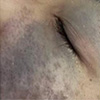

太田痣,作为一种常见的真皮层黑色素细胞增多症,常表现为面部单侧分布的青灰色或蓝褐色斑片。虽属良性病变,但其对容貌的影响往往给成年患者带来沉重的心理负担。许多人在寻求改善时,常对治疗周期的长短、费用的构成因素以及南京地区优质医疗资源的选择心存疑虑。深入解析这些关键问题,有助于患者建立科学的认知,从而做出理性的诊疗决策。

成人太田痣激光治疗次数多吗?费用受哪些因素影响?南京胎记医院哪家好?关于成人太田痣激光治疗的次数,需明确的是,这并非一个固定的数字,而是受多重变量影响的动态过程。相较于婴幼儿,成人皮肤代谢相对缓慢,且色素颗粒往往沉积更深、分布更密,因此治疗周期通常较长。激光治疗利用“选择性光热作用”原理,将特定波长的光束精准作用于真皮层黑色素,将其击碎后由人体免疫系统逐步代谢排出。这一生理过程需要时间,两次治疗之间需预留足够的修复间隔,以避免皮肤损伤。